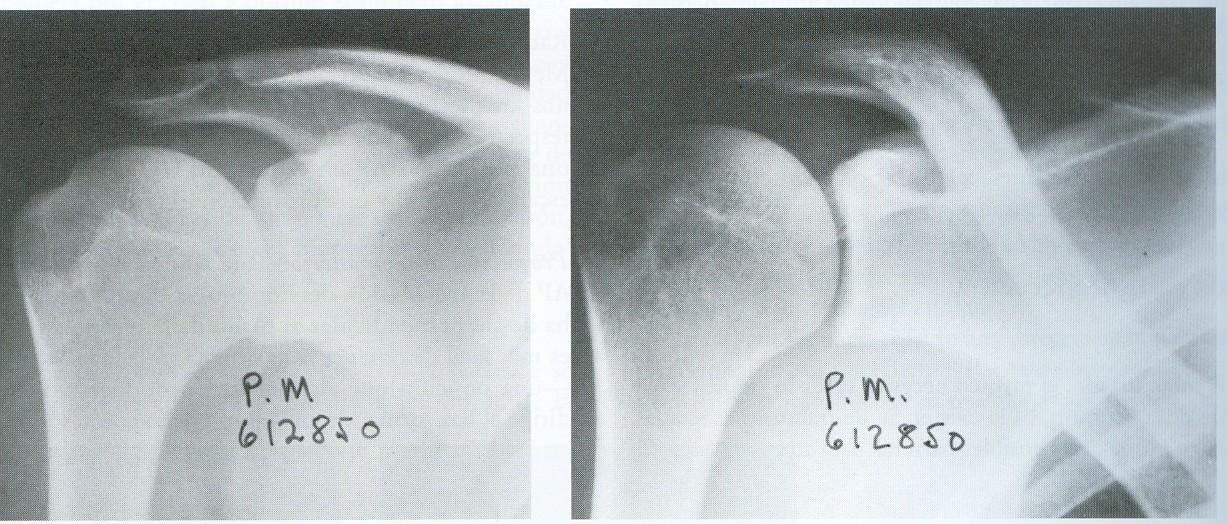

A-P en Plano Torácico y Escapular

A-P en Plano Toracico y Escapular

Lateral en el Plano Escapular

Axilar • Axilar lateral De Velpeau